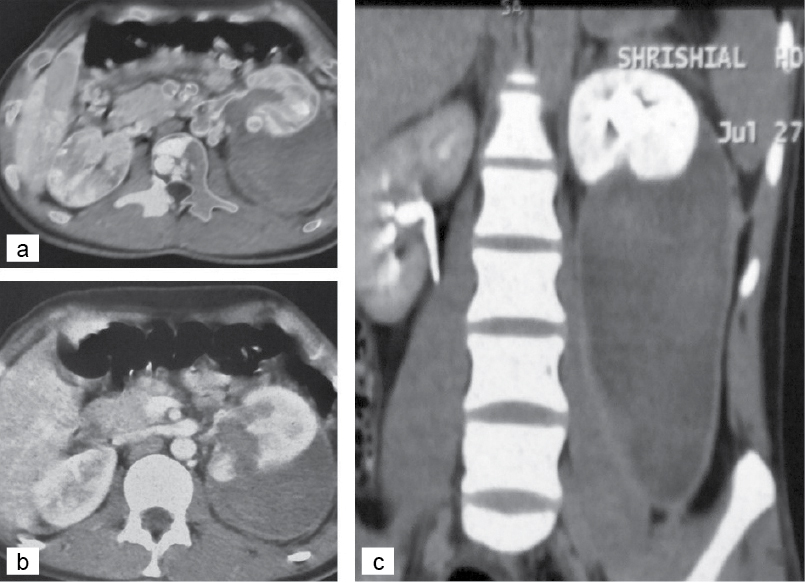

Contrast CT (Fig. 1) done revealed Grade IV renal injury in 2 patients and Grade V injury in 1 patient. Focal intensely enhancing areas were noted at the site of renal parenchymal lacerations suggestive of pseudoaneurysms. Perirenal collection was also noted. In view of the persistent bleeding and presence of pseudoaneurysms, the patients were counseled for complete endovascular embolization.

Figure 1. (a) CT scan showing a huge perirenal collection. (b) scan showing lower polar laceration communicating with renal pelvis. (c) CT scan showing a huge perirenal collection trickling down the fascia of Gerota.